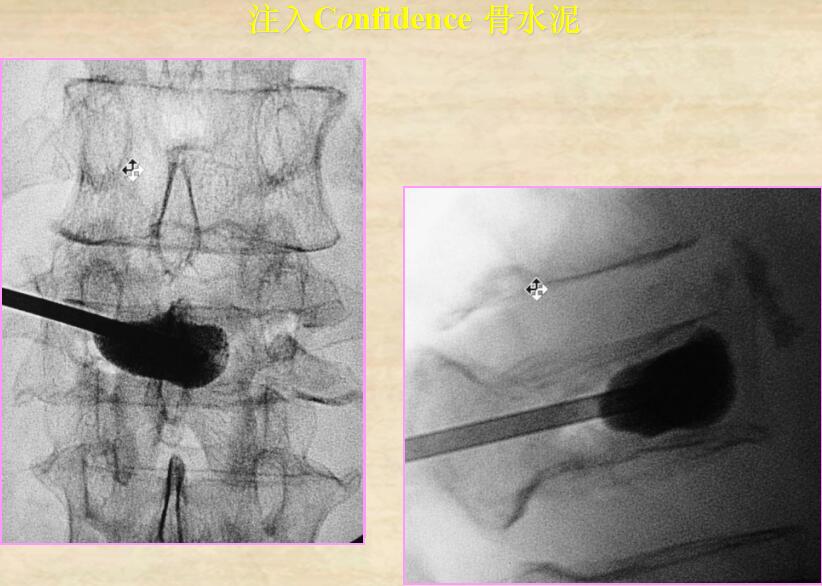

改良型高粘度顯影骨水泥(PMMA),采用高粘度骨水泥加壓注入的方式,調(diào)和后即呈牙膏狀高粘度狀態(tài),無液態(tài)相;工作時間長;可清晰顯影,進一步避免骨水泥泄漏等并發(fā)癥的發(fā)生。

【手術過程演示,神奇的椎體成形術原來如此簡單!】

2、調(diào)和骨水泥裝入容器

5、手術結果